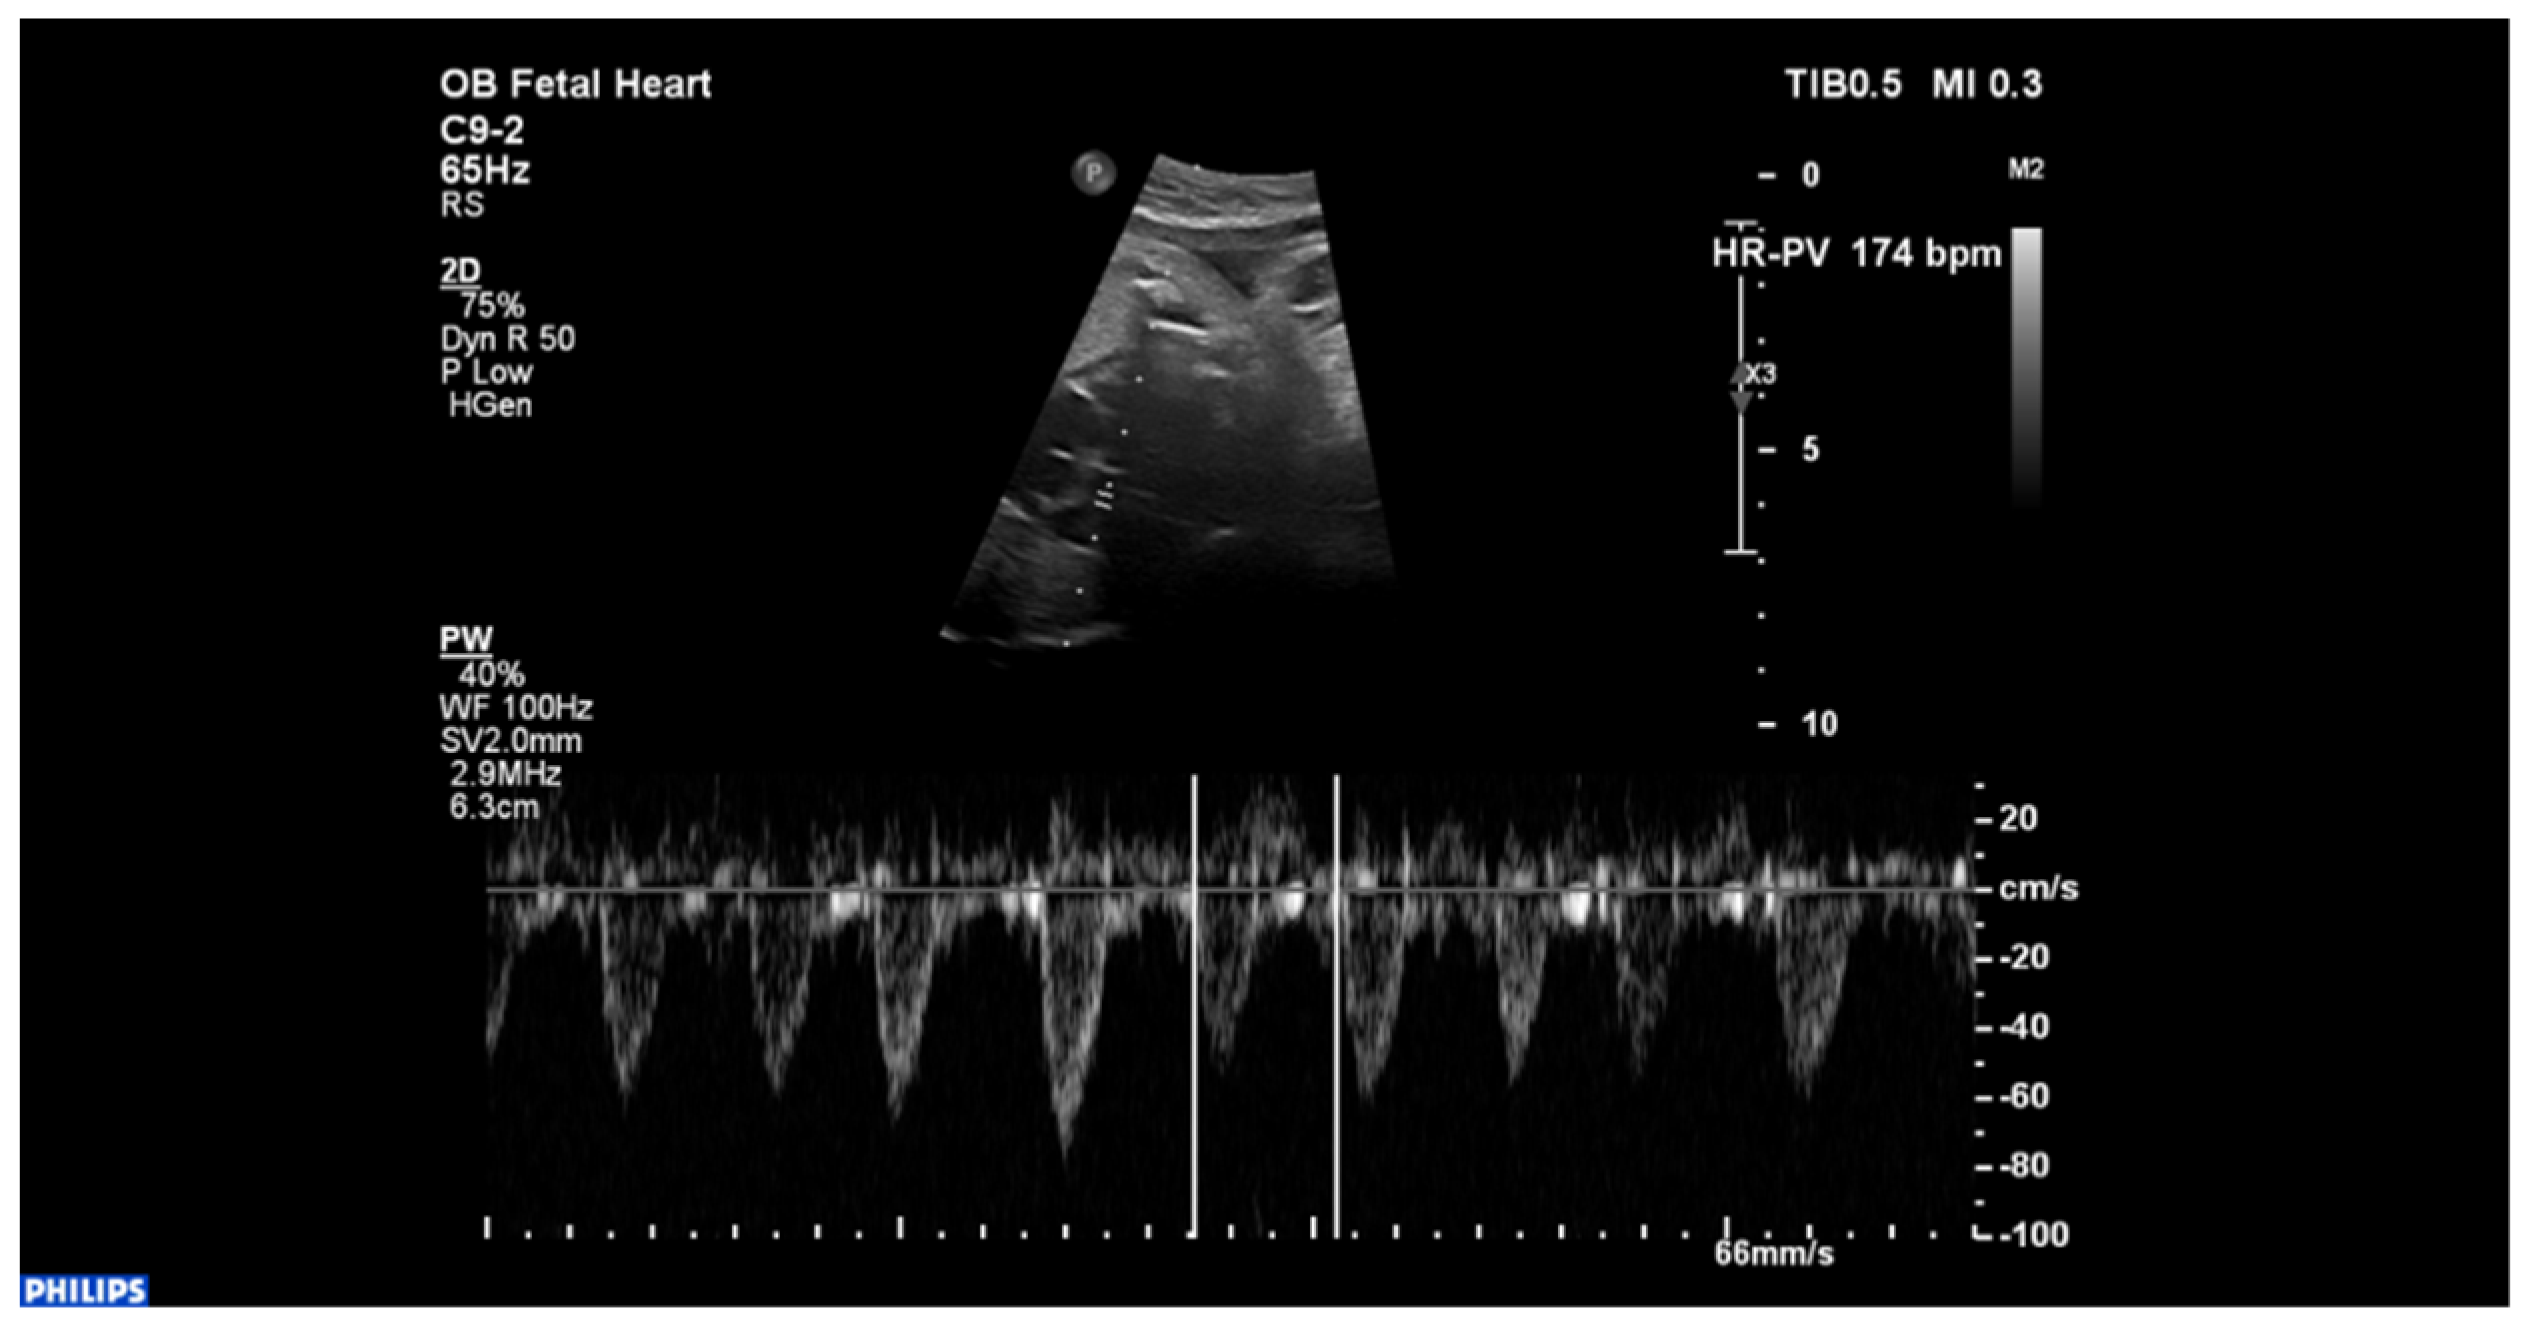

2. Case Description